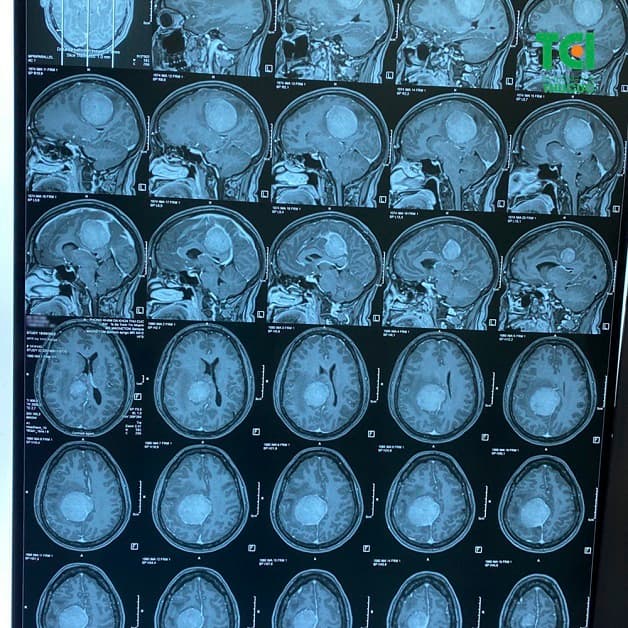

Bệnh nhân đi khám vì triệu chứng đau đầu, mất ngủ, tê bì cánh tay chụp cộng hưởng từ MRI não thì phát hiện có khối u to gây tăng áp lực nội sọ.